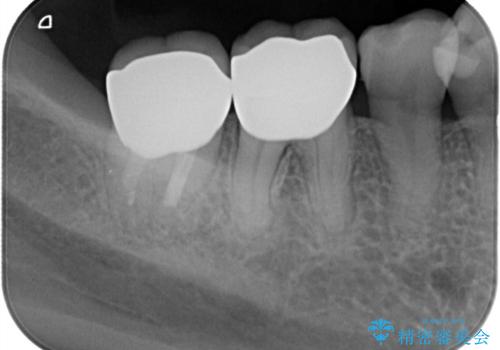

- 他院で治療した被せ物が取れたを主訴に来院された患者様です。被せものが外れた隣の歯もプラスチックの詰め物の劣化や歯に亀裂があったためオールセラミッククランで治療を行いました。

- 242,000円(仮歯11,000円×2本、オールセラミッククラウンスタンダード110,000×2本)費用は治療当時の料金となります

昔詰めたプラスチックの詰め物の範囲が大きいのと破折のリスクや強度の担保のためインレーではなくクラウンで治療を行いました。